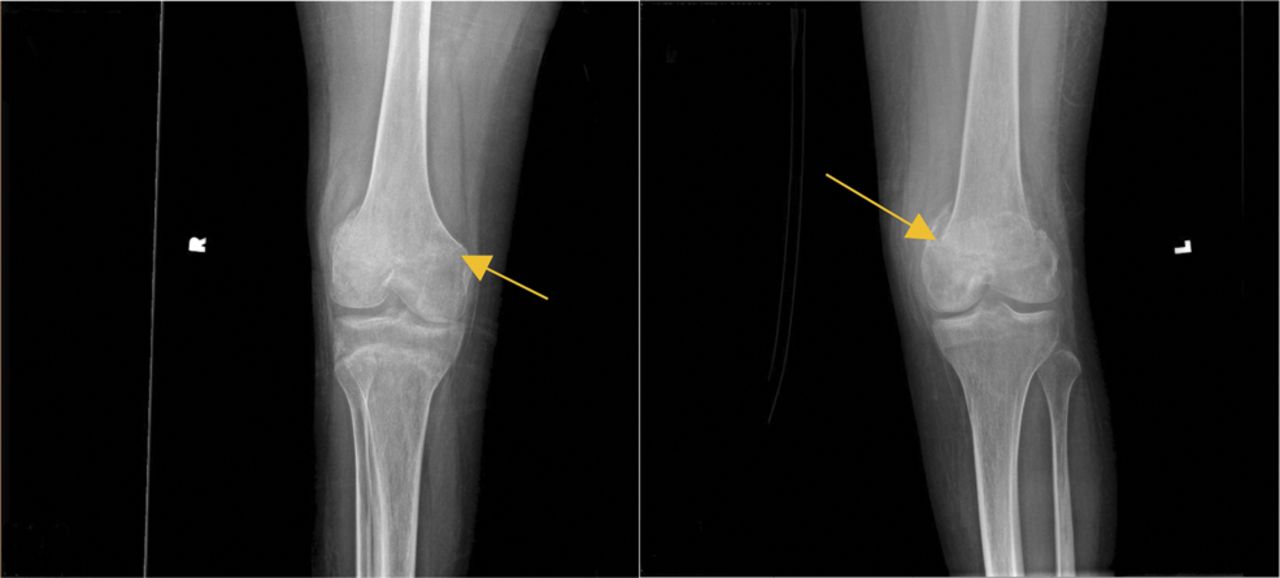

空气或脂肪栓子引起急性micropulmonary栓子紧随其后的大脑似乎栓子,鉴于呼吸之前投诉后的急性神经改变病人的下降。然而,最初,没有明显的栓子来源。没有明显的瘀伤的迹象显示骨折。在医院的第二天,出血点发达在腋窝和腹股沟。评估对隐匿性骨折骨调查显示新皮质step-offs沿横向方面的远端股骨metaphyses双边,可疑为轻微影响,nondisplaced,不完全骨折。随后的股骨和胫骨腓骨x射线证实了这些发现。整形外科手术把膝盖防盗控制系统。病人被诊断为脂肪栓塞综合征(包括脑脂肪栓塞)。虽然好处可用数据有限,甲基强的松龙(100毫克(四)日常管理1周,1周锥度。他的课程是复杂的脑水肿和脑积水,要求渗透疗法和外部心室排水位置。

SCI患者已知高长骨骨折的风险,这发生在一个年度发病率2% - -6%的人口。1,2在这种情况下,x射线显示只有轻微影响,nondisplaced骨折,提高是否SCI患者的脂肪栓塞的风险甚至轻微骨折。